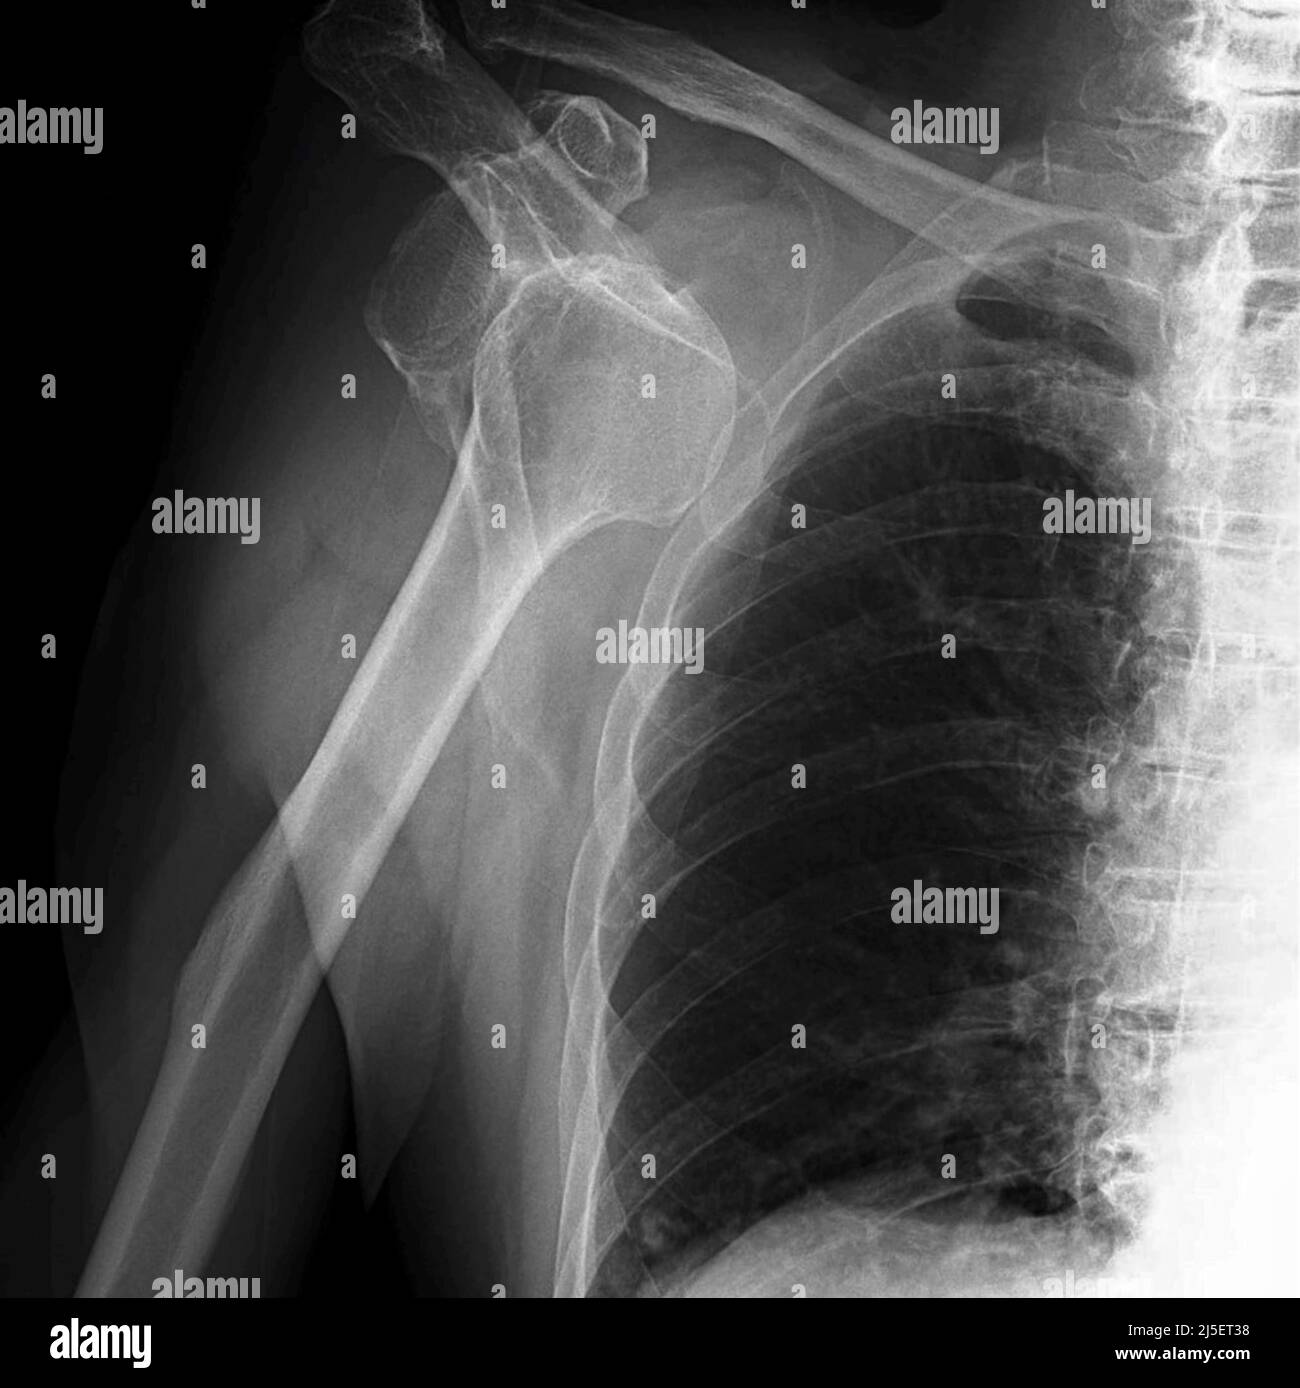

Can An X Ray Show A Dislocated Shoulder . The humeral head is subcoracoid in. If it is dislocated, a doctor will rotate your arm back into place. Healthcare providers use a shoulder x. Anteroposterior radiograph shows luxatio erecta, or inferior dislocation of the shoulder. The arm is abducted, elevated, and fixed. A dislocated shoulder is one where the humeral head or upper part of the arm bone is no longer. A health care provider inspects the affected area for tenderness, swelling or deformity and checks for signs of nerve or blood vessel.

A health care provider inspects the affected area for tenderness, swelling or deformity and checks for signs of nerve or blood vessel. Healthcare providers use a shoulder x. If it is dislocated, a doctor will rotate your arm back into place. The arm is abducted, elevated, and fixed. The humeral head is subcoracoid in. A dislocated shoulder is one where the humeral head or upper part of the arm bone is no longer. Anteroposterior radiograph shows luxatio erecta, or inferior dislocation of the shoulder.